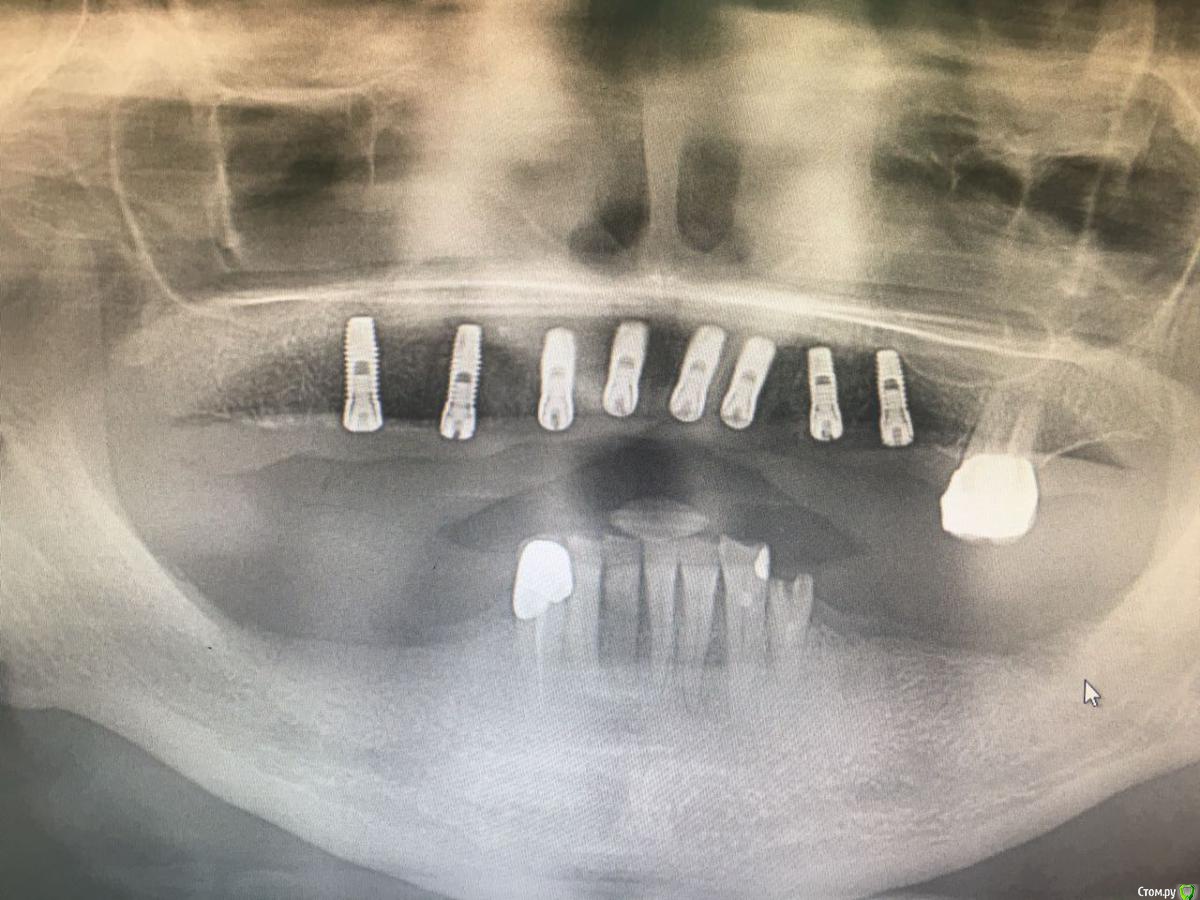

ksenistom Опубликовано 3 февраля, 2017 Поделиться Опубликовано 3 февраля, 2017 Коллеги,подскажите в данном случае есть вариант протезирования без мультиюнитов?Система дентиум.И вообще есть на дентиуме мультиюниты,я с ней недавно начала работать?!Подобная работа на альфе была,там без сомнения мультиюниты выравнивали оси.Снимок сделан сразу после установки формирователей. Ссылка на комментарий

ksenistom Опубликовано 7 февраля, 2017 Автор Поделиться Опубликовано 7 февраля, 2017 Какую конструкцию планируете? Если не секрет. Мульты, у Дэнтиума есть. Кажется даже взаимозаменяемые на Имплантиум.Какую конструкцию планируете? Если не секрет. Мульты, у Дэнтиума есть. Кажется даже взаимозаменяемые на Имплантиум.Предложем несколько вариантов:1. Цельноциркониевая конструкция на титановой балке2. Угловые абатменты с цементной фиксацией Ссылка на комментарий

suballex Опубликовано 11 февраля, 2017 Поделиться Опубликовано 11 февраля, 2017 Делайте временные. На них отрабатывайте наполненность мягких тканей, форму и прикус. В зависимости от результата - принимайте решение о постоянной конструкции. Вариантов - масса. Можно тремя мостами на инд.абатментах на цементе, или дистально на винты, фронт - цемент. Можно подкову на инд.абатментах. Можно первичную балку и одиночки. Можно без первичной балки. Можно тринию Зависит от объема восстановления. Если от режущего до промывного будет миллиметров 25, то какой там циркон цельный поставишь? В общем, временные, временные и еще раз временные. 2 Ссылка на комментарий

руслан64 Опубликовано 12 февраля, 2017 Поделиться Опубликовано 12 февраля, 2017 Не рассматривайте мультики Дентиум. Очень слабый металл, какие то "плюшевые", извините. Того и глядишь, прокрутится винт. Лучше как выше сказали, отработать на провизорах, инд. абатменты с цем фиксацией подковы, из чего решайте с пациентом. Делал бы несъемную конструкцию.Да..и есть конечно вопросы по планированию..но это, как грится в след. серии)) Ссылка на комментарий